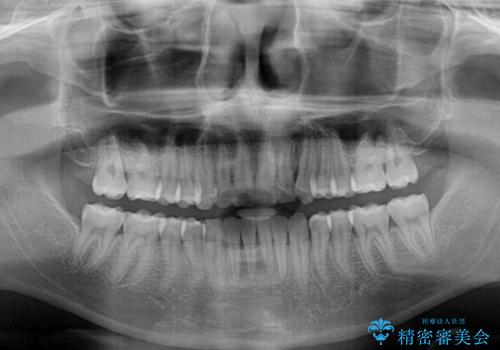

上顎骨を思い通りに拡大できたため、当初の計画通りに非抜歯矯正で仕上げることができました。